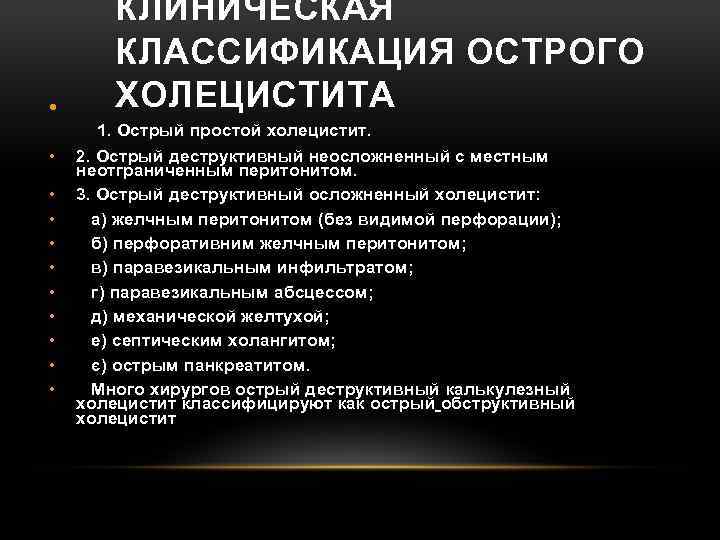

КЛИНИЧЕСКАЯ КЛАССИФИКАЦИЯ ОСТРОГО ХОЛЕЦИСТИТА • 1. Острый простой холецистит. • • • 2. Острый деструктивный неосложненный с местным неотграниченным перитонитом. 3. Острый деструктивный осложненный холецистит: а) желчным перитонитом (без видимой перфорации); б) перфоративним желчным перитонитом; в) паравезикальным инфильтратом; г) паравезикальным абсцессом; д) механической желтухой; е) септическим холангитом; є) острым панкреатитом. Много хирургов острый деструктивный калькулезный холецистит классифицируют как острый обструктивный холецистит

КЛИНИЧЕСКАЯ КЛАССИФИКАЦИЯ ОСТРОГО ХОЛЕЦИСТИТА • 1. Острый простой холецистит. • • • 2. Острый деструктивный неосложненный с местным неотграниченным перитонитом. 3. Острый деструктивный осложненный холецистит: а) желчным перитонитом (без видимой перфорации); б) перфоративним желчным перитонитом; в) паравезикальным инфильтратом; г) паравезикальным абсцессом; д) механической желтухой; е) септическим холангитом; є) острым панкреатитом. Много хирургов острый деструктивный калькулезный холецистит классифицируют как острый обструктивный холецистит